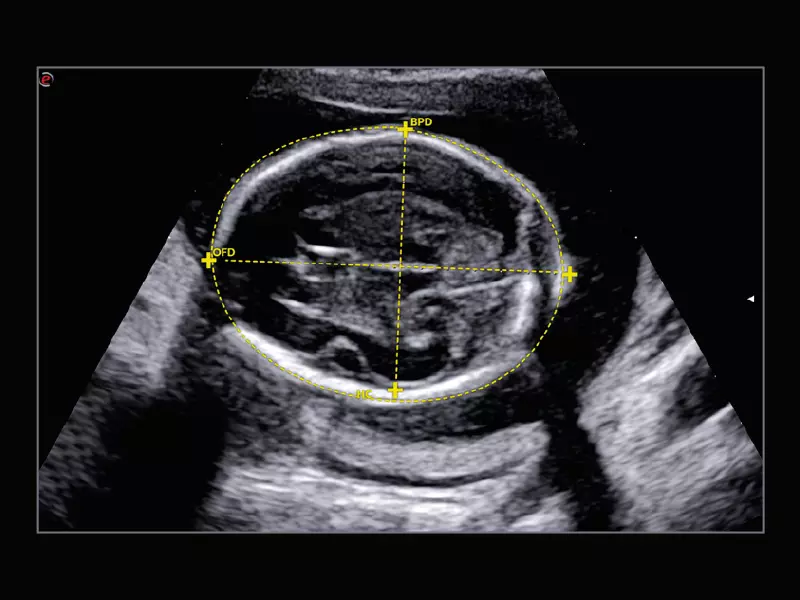

MyLab™X90 - Automatic Plan recognition Automatic biometric plan recognition for fetal measurements

MyLab™X90 - Automatic Plan recognition Automatic biometric plan recognition for fetal measurements

MyLab™X90 - AutoOB Automatic proposals for fetal biometric measurements

MyLab™X90 - AutoOB Automatic proposals for fetal biometric measurements